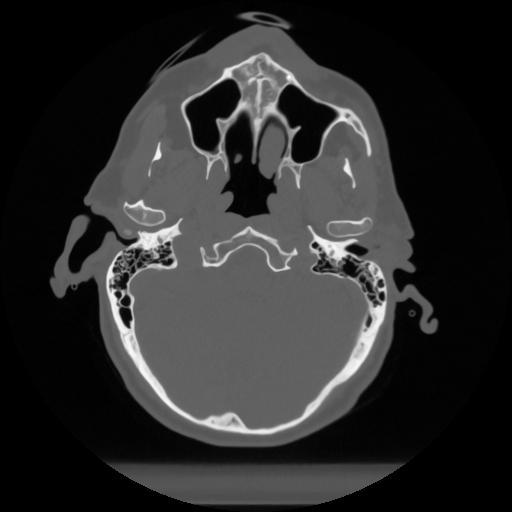

12 P.BLANDAS,,Vol,0.5,P.BLANDAS,,